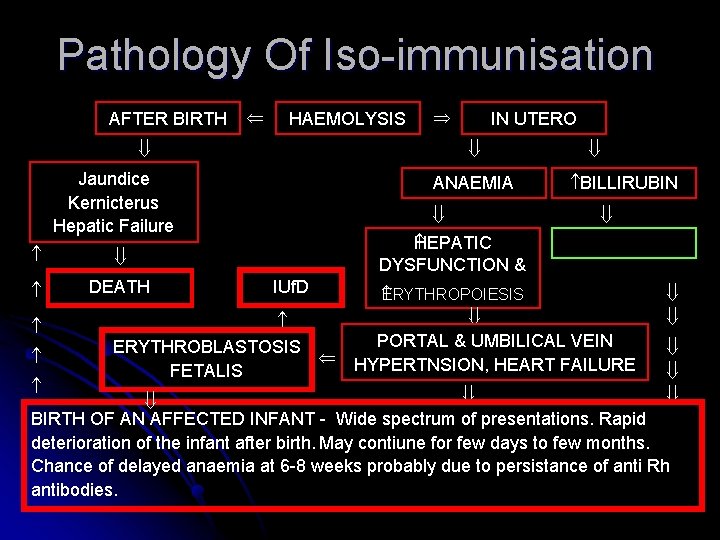

Pathology Of Iso-immunisation AFTER BIRTH HAEMOLYSIS Jaundice Kernicterus Hepatic Failure DEATH ANAEMIA BILLIRUBIN EPATIC H DYSFUNCTION & IUf. D ERYTHROBLASTOSIS FETALIS IN UTERO ERYTHROPOIESIS PORTAL & UMBILICAL VEIN HYPERTNSION, HEART FAILURE BIRTH OF AN AFFECTED INFANT - Wide spectrum of presentations. Rapid deterioration of the infant after birth. May contiune for few days to few months. Chance of delayed anaemia at 6 -8 weeks probably due to persistance of anti Rh antibodies.